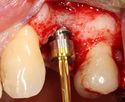

A series of slow-speed drills create and gradually enlarge a site in the jaw for the implant to be placed. The hole is called an osteotomy.

Once the bone is exposed, a series of drills create and gradually enlarge a site (called an osteotomy) for the implant to be placed.

The implant fixture is turned into the osteotomy. Ideally, it is completely covered by bone and has no movement within the bone.

A healing abutment is attached to the implant fixture and the gingiva flap is sutured around the healing abutment.

A healing abutment is attached to the implant fixture, and the flap of gingiva is sutured around the healing abutment.

يتم اجراء جراحة الأسنان في العيادة تحت ظروف معقمة، من قبل طبيب أسنان متخصص في زراعة الأسنان و/أو جراحة الفم والفك. يتم تخدير المريض بواسطة حقنة بمخدر موضعي في منطقة دواعم السن، كما هو الحال في علاجات الأسنان العادية (في بعض الأحيان هناك حاجة بتوسيع نطاق التخدير، وفقاً لموقع الغرسات).

اذا كان العظم على استعداد لتلقي الزرع (أحيانا بعد سلسلة علاجات مسبقة)، يمكن البدء بعملية زرع الاسنان. يتم تثبيت المسامير المعدنية اللولبيه براغي، بعظم الفك. في سلسلة اخرى من العلاجات بعد فترة من ادخال البراغي، تبدا عمليات اعادة البناء عن طريق أخذ القياسات وانشاء التاج/الجسر. عندما يدور الحديث عن فترة الانتظار بين تركيب الغرسات وبين تنفيذ الاستبناء النهائي، فان هنالك اكثر من نهج واحد. النهج المتبع غالبا هو الانتظار لمدة 6 أسابيع على الأقل حتى تلتئم الانسجة، وأحيانا تصل فترة الانتظار لعدة شهور.